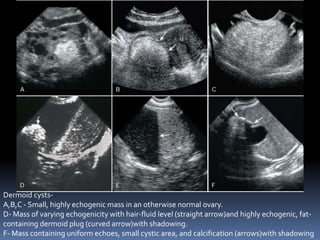

This document contains an image gallery from Dr. Mohit Goel showing various uterine anomalies and ovarian cysts. It includes images of an arcuate and unicornuate uterus, endometritis, a twisted ovarian pedicle, dermoid cysts of varying sizes and echogenicity containing hair, fat, and calcifications, and a combination dermoid cyst showing both mesh and plug structures. The gallery provides ultrasound images of different gynecological conditions for medical education and reference.